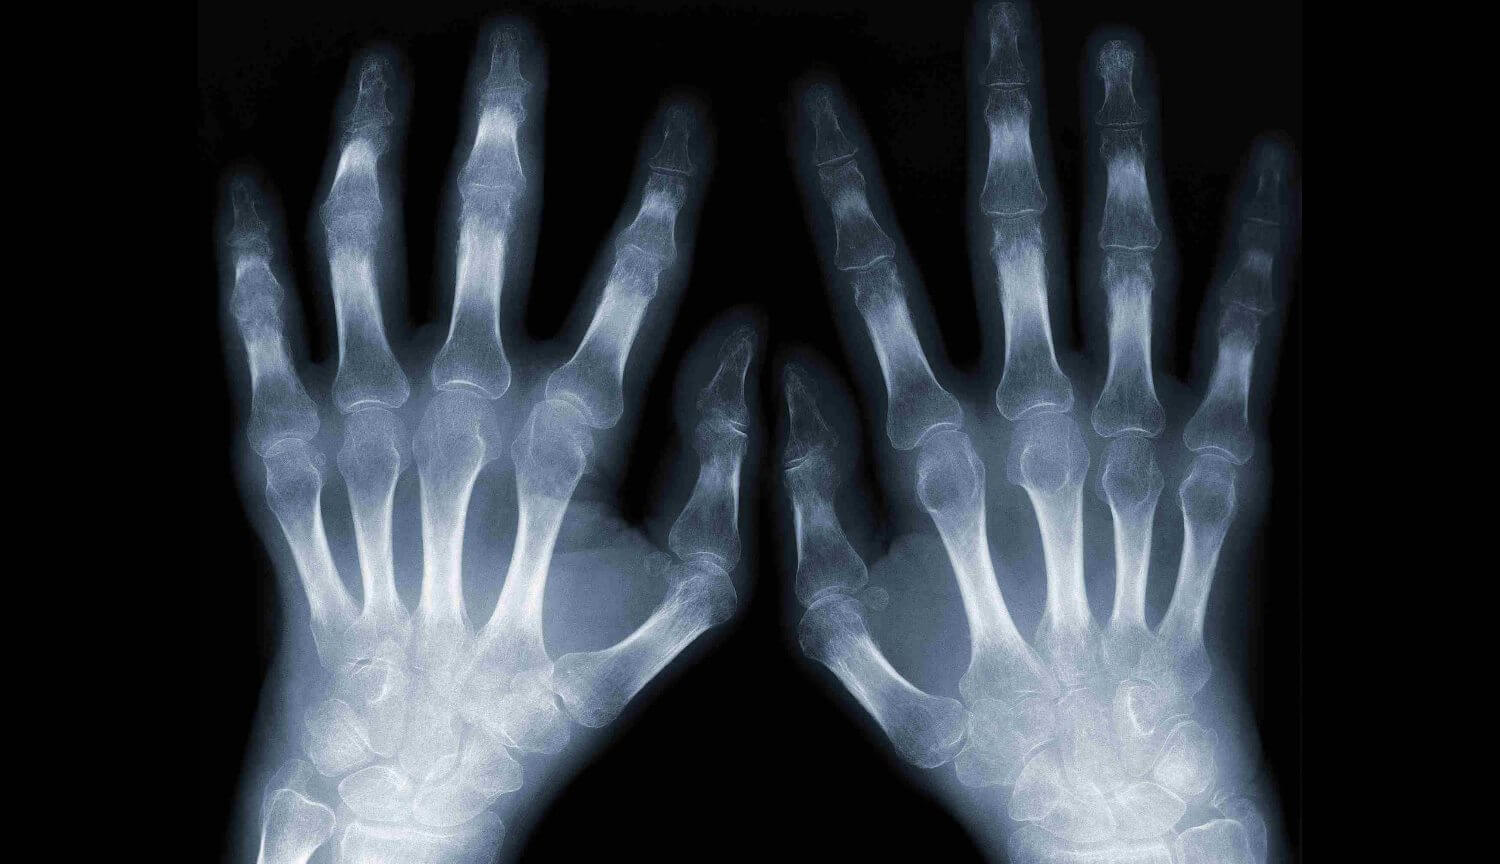

Анализ тканей и хрящей показал, что отсутствие гравитации уже спустя 30 дней вызвало у мышей признаки остеоартрита. Исследователи объяснили, что даже если мыши тренируются и совершают активные движения, их организму не хватает той нагрузки, которая есть в земных условиях. По словам Джейми Фицджеральда, в условиях гравитации необходимую для поддержания здоровья суставов нагрузку можно получить даже при обычной ходьбе.

Самое страшное, что после возвращения на Землю хрящи восстанавливаются с очень большим трудом — скорее всего, астронавтам и космическим туристам придется испытывать проблемы со здоровьем очень долгое время.